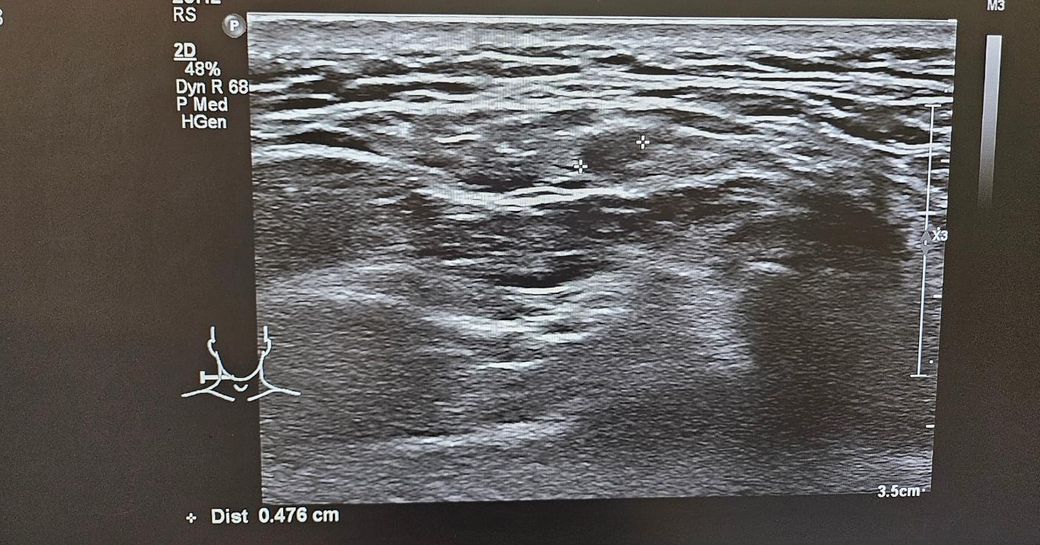

경부 초음파찍었는데 초음파 사진좀 봐주세요.. .

목통증이 있어서 초음파를 했는데

여러개가 부어있다고 하셨습니다

• 1번 째 사진

초음파 소견으로는 림프절들이 보이며 부어 있다 정도로 보입니다. 이외에 특별하나 소견이 따로 있거나 해 보이지 않습니다. 약물 치료를 하여도 회복이 되지 않다면 추가적으로 약물 복용을 해주며 경과를 지켜보거나 보다 정밀 검사를 통해서 다른 문제는 없는지 감별해보는 방향이 있겠습니다. 이비인후과적으로 재차 상담을 받아보시는 것을 권고드립니다.